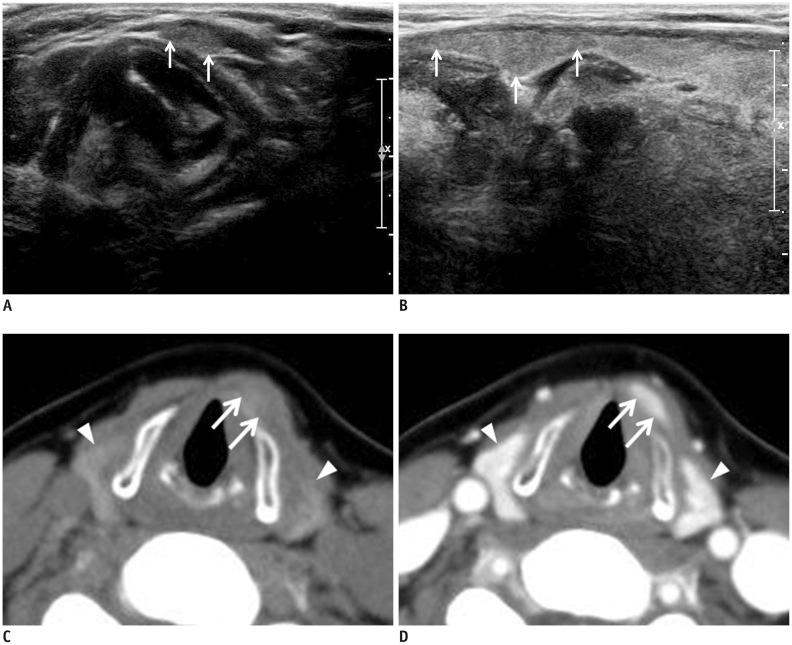

To compare the detection rates of the pyramidal lobe of the thyroid gland (TPL) using ultrasonography (US) and computed tomography (CT) in a prospective multi-center study.

We enrolled 582 patients who underwent neck CT at six institutions. Each radiologist prospectively evaluated the presence and features of TPLs on thyroid US. Radiologists were divided into two groups according to their previous experience in detecting TPL on US or CT. The same radiologist also retrospectively assessed CT findings, blinded to the corresponding US findings.

The pyramidal lobe of the thyroid glands were detected in 230 cases (39.5%) on US and in 276 cases (47.6%) on CT. The TPL detection rate at the six institutions ranged from 22.0% to 59% for US and from 34.1% to 59% using CT. There were significant differences between US and CT in the detection rate, length, anteroposterior diameter, volume, and superior extent of TPL (p ≤ 0.027). The TPL detection rates on both US and CT (p < 0.001) differed significantly according to the experience level of the radiologists. When the CT result was used as a reference standard, the sensitivity, specificity, positive and negative predictive values, as well as the accuracy of US for TPL detection were 72.6%, 91.5%, 89.3%, 77.3%, and 82.1%, respectively.

Our prospective multicenter study revealed that US could detect TPL with relatively high diagnostic accuracy compared to CT. Because the detection rate of TPL varied significantly according to the radiologists' level of experience, careful inspection is necessary to avoid imaging pitfalls and ensure appropriate evaluation of TPL on both US and CT.